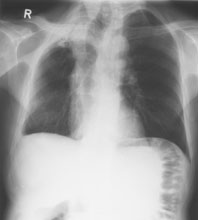

Ein 71-jähriger Italiener beklagt sich über einen reduzierten Allgemeinzustand und subfebrile Temperaturen. Er raucht seit 45 Jahren.

Husten und Auswurf hätte er immer gehabt, berichtet der Patient. Mit der Frage nach einem Infiltrat wird ein Röntgenbild verordnet:

Thorax pa

Welche Befunde imponieren (mehrere richtige Antworten möglich)?